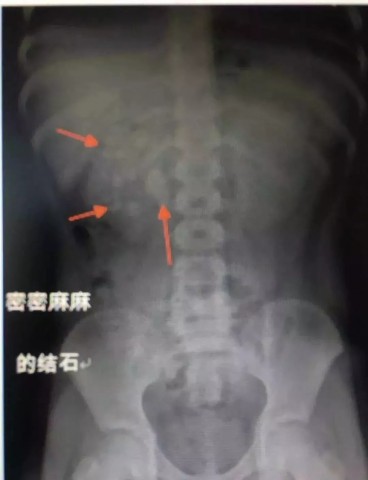

在X光图像下,医生发现小轩的双侧肾脏都内藏乾坤,密密麻麻的分布着大小不等的结石。

小轩这种情况,其中,最大的结石长约2.7厘米,宽约1.7厘米,体积堪比鹌鹑蛋,不但造成了尿路堵塞,还导致了右肾中度积水。